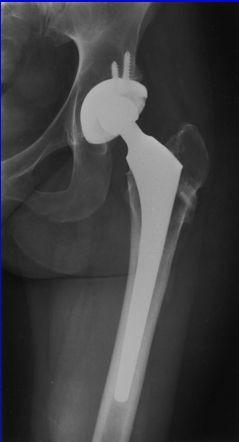

Artroplastia Total de Cadera

Artroplastia Total de Cadera indicaciones  osteonecrosis de la cabeza femoral con cambios y lesión severa del cartílago articular de la cabeza y pérdida del cartílago acetabular.  con afectación extensa o colapso de la cabeza femoral que tiene síntomas suficientes.  Pacientes mayores o con bajas demandas funcionales.

Artroplastia Total de Cadera contraindicacion  pacientes jóvenes con una osteonecrosis de la cabeza femoral en estadío precoz .  pacientes con un riesgo excesivo de complicaciones con una artroplastia total (por ejemplo, aquellos con un hábito alcohólico grave y permanente que tendrían un riesgo excesivo de luxación de una prótesis total)